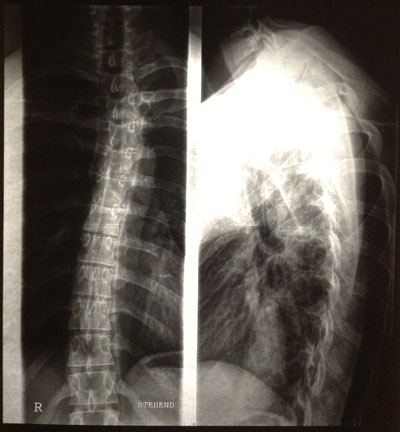

So, hier sind sie:

Was sagt ihr dazu? Welche Therapie ist zu empfehlen. Schroth zahlt die Kasse hier nicht. Irgendwelche Gedanken?

Die Skoliose ist ja hauptsächlich im Bereich der BWS, wie man erkennen kann.

- Nackenbereich

- Foto.jpg (28.37 KiB) 14515 mal betrachtet

Kyphose (seitliche Aufnahme) müsste im grünen Bereich liegen

ich finde die Kyphose schon relativ deutlich im BWS-Bereich, die skoliotische Abweichung ebenfalls. Eventuell macht die Kombination von beidem die von Dir beschriebene Problematik. Aber das lässt sich via Internet nicht definitiv sagen. Dazu müsste man zum einen Dich "live" vor sich stehen haben und zum anderen die Bilder auf Folie in Originalgröße. An diesen kann man auch den Winkel ausmessen. Ausdrucke eignen sich zur Befundung nicht.

Es fällt eine Steilstellung der HWS, eine leichte Hyperkyphose und eine leichte Skoliose auf und mit Schroth könntest Du wahrscheinlich ganz gute Ergebnisse erzielen.